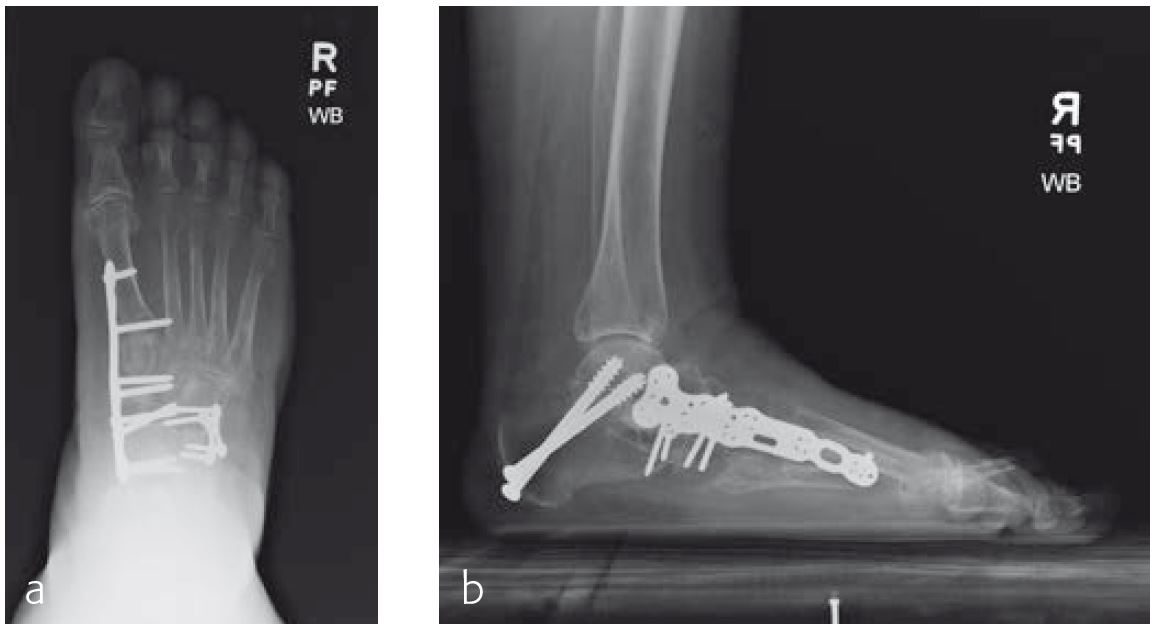

Case 2: 70-year-old patient

A 70-year-old female patient (Fig 1) had a long history of increasing painful deformity of her foot. She also noted increasing gait problems. There was no history of initial trauma. The examination showed severe rigid flatfoot deformity.

An extended triple arthrodesis was performed. Medially, the new Medial Column Plate was used, securing the talonavicular, naviculocuneiform, and tarsometatarsal joints (Fig 2). The X-plate is lateral and secured the calcaneo-cuboid joint. Two 7.3 mm screws were used to secure the subtalar joint.